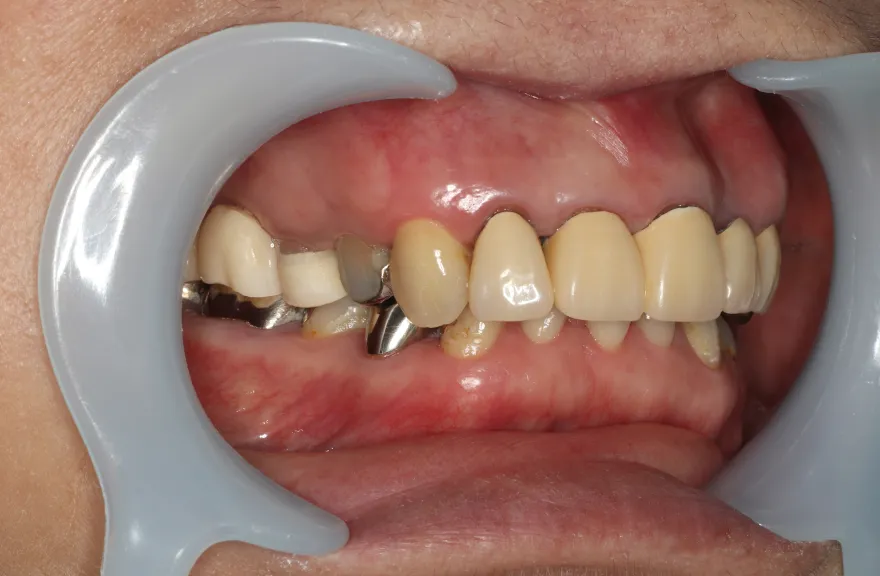

右上の奥歯が取れたということで来院されました。

各所の金属は昔に治療されたもので、外してみるとどれも虫歯になっていました。

一つずつ虫歯治療を行い、インプラント治療、矯正治療を並行して行いました。 - 治療費用・方針

各所虫歯に侵食されていましたが、歯を残すことができたのでインプラントの数をおさえることができました。

下の前歯が先天的に1本欠損しており、そのため噛み合わせを構築することが難しいケースでした。矯正治療を併用することで前歯と奥歯をバランスよく噛ませることに成功しました。